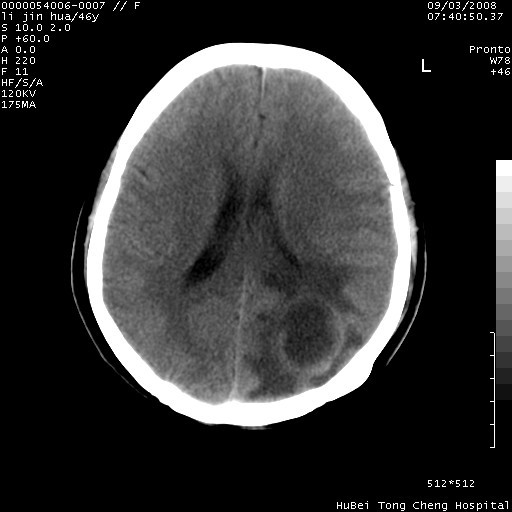

以下是引用panyishengct在2008-9-6 1:47:00的发言:[br]病史?[br]左侧枕/顶叶见一等/低混杂密度占位,壁完整,厚薄较均匀,其前方似有一类似小病灶,周围有水肿带,请结合病史考虑,脓肿可能,不排外转移瘤或胶质瘤,建议增强扫描。